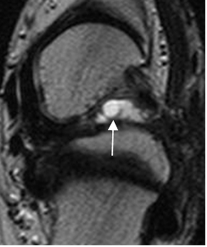

Fig 108. Sindrome del seno del tarso.

A: RM coronal en T1. Imagen hipointensa localizada en el seno del tarso, que reemplaza la grasa.

B: RM axial en T1 y C: RM axial en T2. Tejido inflamatorio en el seno del tarso, hipointenso en ambas secuencias por fibrosis crónica, que rodea los tendones peroneos (Flechas).